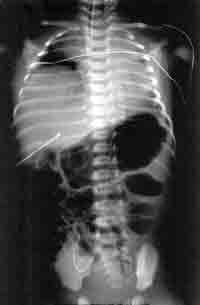

The baby was started on CPAP via nasal prongs for 1hour, but there was no improvement. He was intubated and mechanically ventilated on these settings: pressure of 18/5, rate of 30/min and FiO2 of 0.24. The stridor disappeared and it was easy to ventilate. Within few hours he had normal blood gases.A

chest Xray was repeated at this time.

the chest X-ray

WHAT IS YOUR INTERPRETATION?